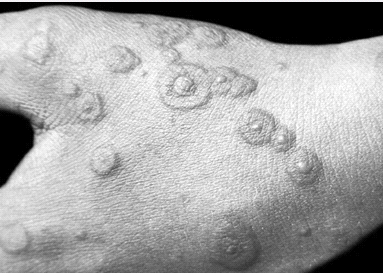

Рис. 1.1. Местная токсико-аллергическая реакция

Многоформная экссудативная эритема (МЭЭ) -

острое, редко рецидивирующее заболевание кожи и слизистых оболочек, возникающее

от разных причин и отличающееся характерным сочетанием многих первичных

элементов сыпи (пятна, папулы, волдыри, пузырьки, пузыри). Может быть вызвана

как инфекцией, так и лекарственными препаратами. Наиболее часто индукторы МЭЭ -

это сульфаниламиды, производные пиразолонового ряда, тетрациклины, барбитураты,

аспирин, диуретики, прогестерон, стрептомицин и др. Первичным элементом

является пятно эритемы, которое в течении двух суток увеличивается до 1-2 см в

диаметре, превращается в папулу. Сформированный элемент имеет резкие границы,

более темные цианотичные края и центр с более светлой розовой полоской между

ними, что придает вид бычьего глаза, ириса, или мишени (рис. 1.2). В центре

пятна может располагаться папула или пузырек. Наиболее частая локализация -

тыльная и ладонная поверхность кистей и подошвенная стоп, разгибательные

поверхности предплечий и голеней, наружные гениталии. Сыпь располагается

симметрично. При распространенной МЭЭ поражается практически все участки кожи,

за исключением волосистой части головы.

Рис.1.2. Округлые отечные розовые пятна в

центре, которого расположен пузырек ("бычьей глаз") при МЭЭ